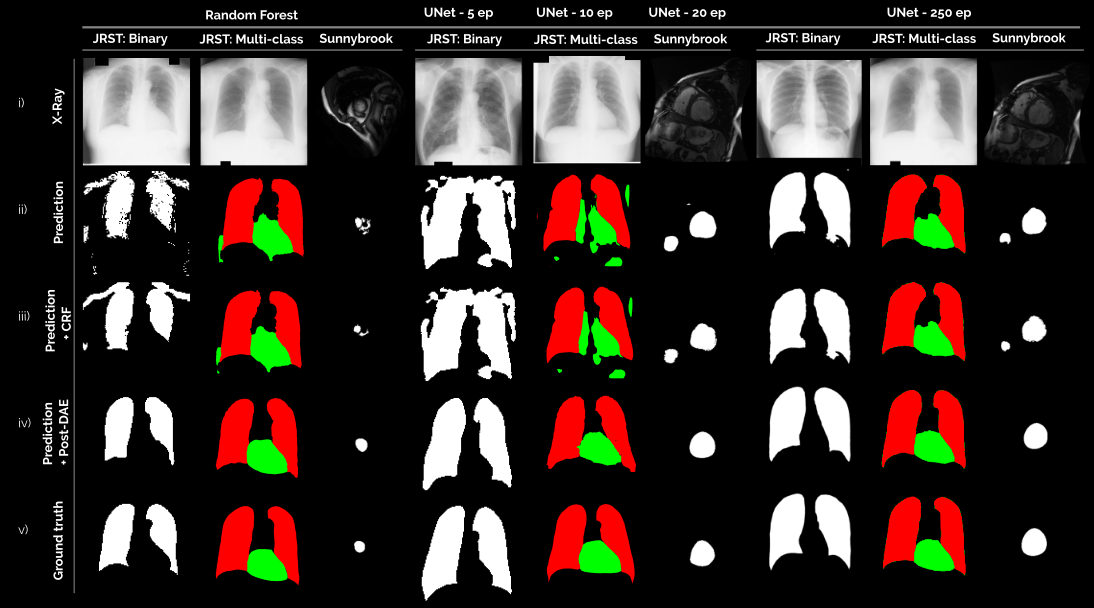

Refer to caption

Figure 2: Predictions obtained with segmentation methods of several qualities: random forest and UNet trained for different number of epochs. We include examples for both binary (white images) and multi-class (color images) segmentation. for: (i) X-Ray or CMR image; (ii) segmentation mask predicted by each baseline method; (iii) segmentation mask after post-processing with a CRF; (iv) segmentation mask after post-processing with our Post-DAE; and (v) ground-truth expert segmentations.

Figure 2 shows some visual examples while Table I and Figure 3 summarize the quantitative results obtained when post-processing segmentations produced by a RF classifier and a UNet. Our best results are in line with those obtained for other deep learning based state-of-the-art methods. For JSRT, recent works [24, 25, 26, 27] report average Dice values for lung and heart ranging from 0.943 [27] to 0.965 [24]. For the Sunnybrook dataset, recent works [28, 29, 30, 31] report average Dice ranging from 0.88 [28] to 0.93 [30] for LV segmentation. Both figures show the consistent improvement achieved when using Post-DAE as a post-processing step, specially in low quality segmentation masks like those obtained by the binary RF model, the multiclass RF considering incomplete tree depths and the UNet trained only for a few epochs. In these cases, substantial improvements are obtained in terms of Dice coefficient and Hausdorff distance (HD), by bringing the erroneous segmentation masks into an anatomically feasible space. In case of segmentations that are already of good quality (like multi-class RF or the UNet trained until convergence), Post-DAE significantly improves the HD, by erasing spurious segmentations that remain even in well trained models, like holes in the lung or small isolated blobs. When compared with CRF post-processing, Post-DAE significantly outperforms the baseline in the context of anatomical segmentation. In terms of running time, the CRF model takes 1.3 seconds while Post-DAE takes 0.76 seconds in a Intel i7-7700 CPU.